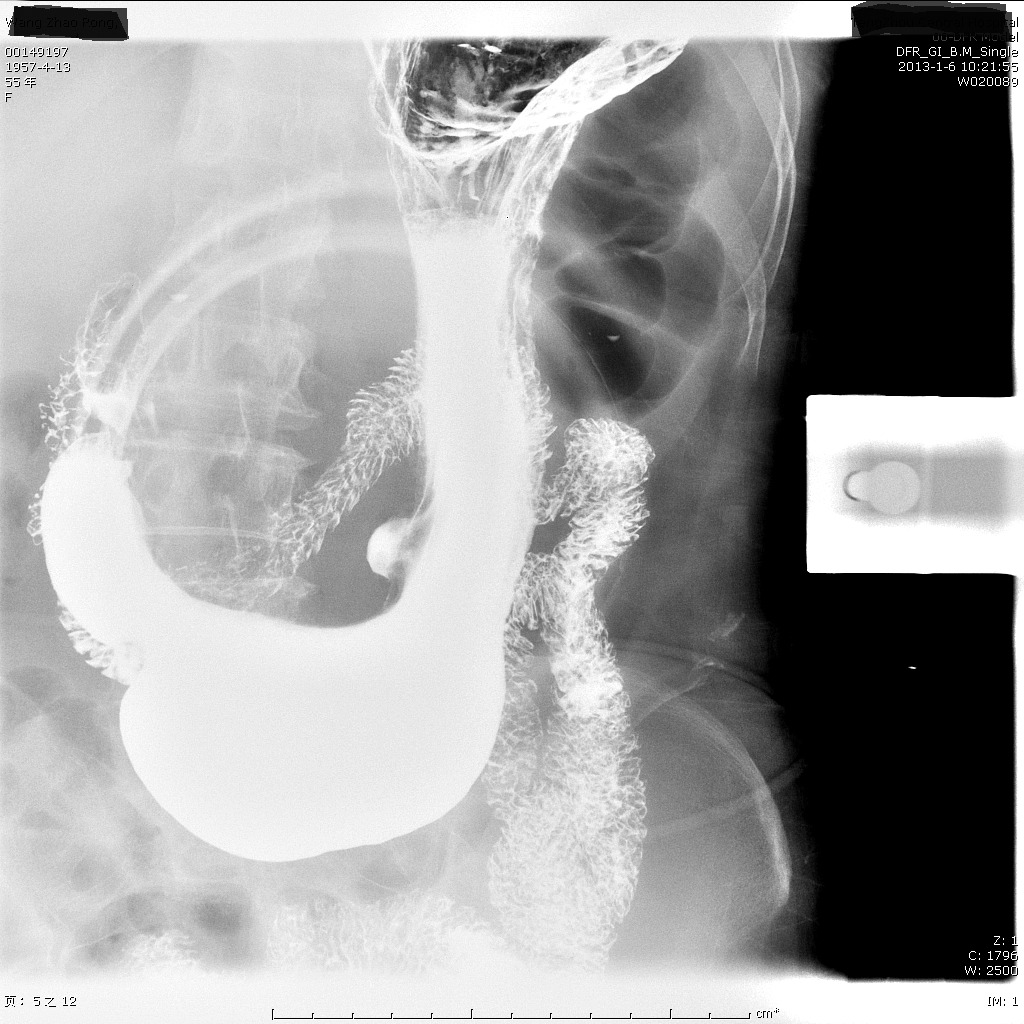

三,上消化道碘水造影

与钡餐造影相同点:

1,同样利用造影剂增加胃肠道管腔和管壁的对比,更好的显示病变。

2,都需要在x线下判断疾病,都不能对病变部位取活检。

与钡餐不同点:

1,碘水为水溶性造影剂,黏膜黏附很少,对溃疡等病变显示不如钡餐。

2,对于观察消化道是否通畅,狭窄,梗阻的程度,碘水造影非常有优势,钡剂秘结成块可能加重梗阻,而碘水即使不能通过梗阻也可以通过胃管吸引出来。